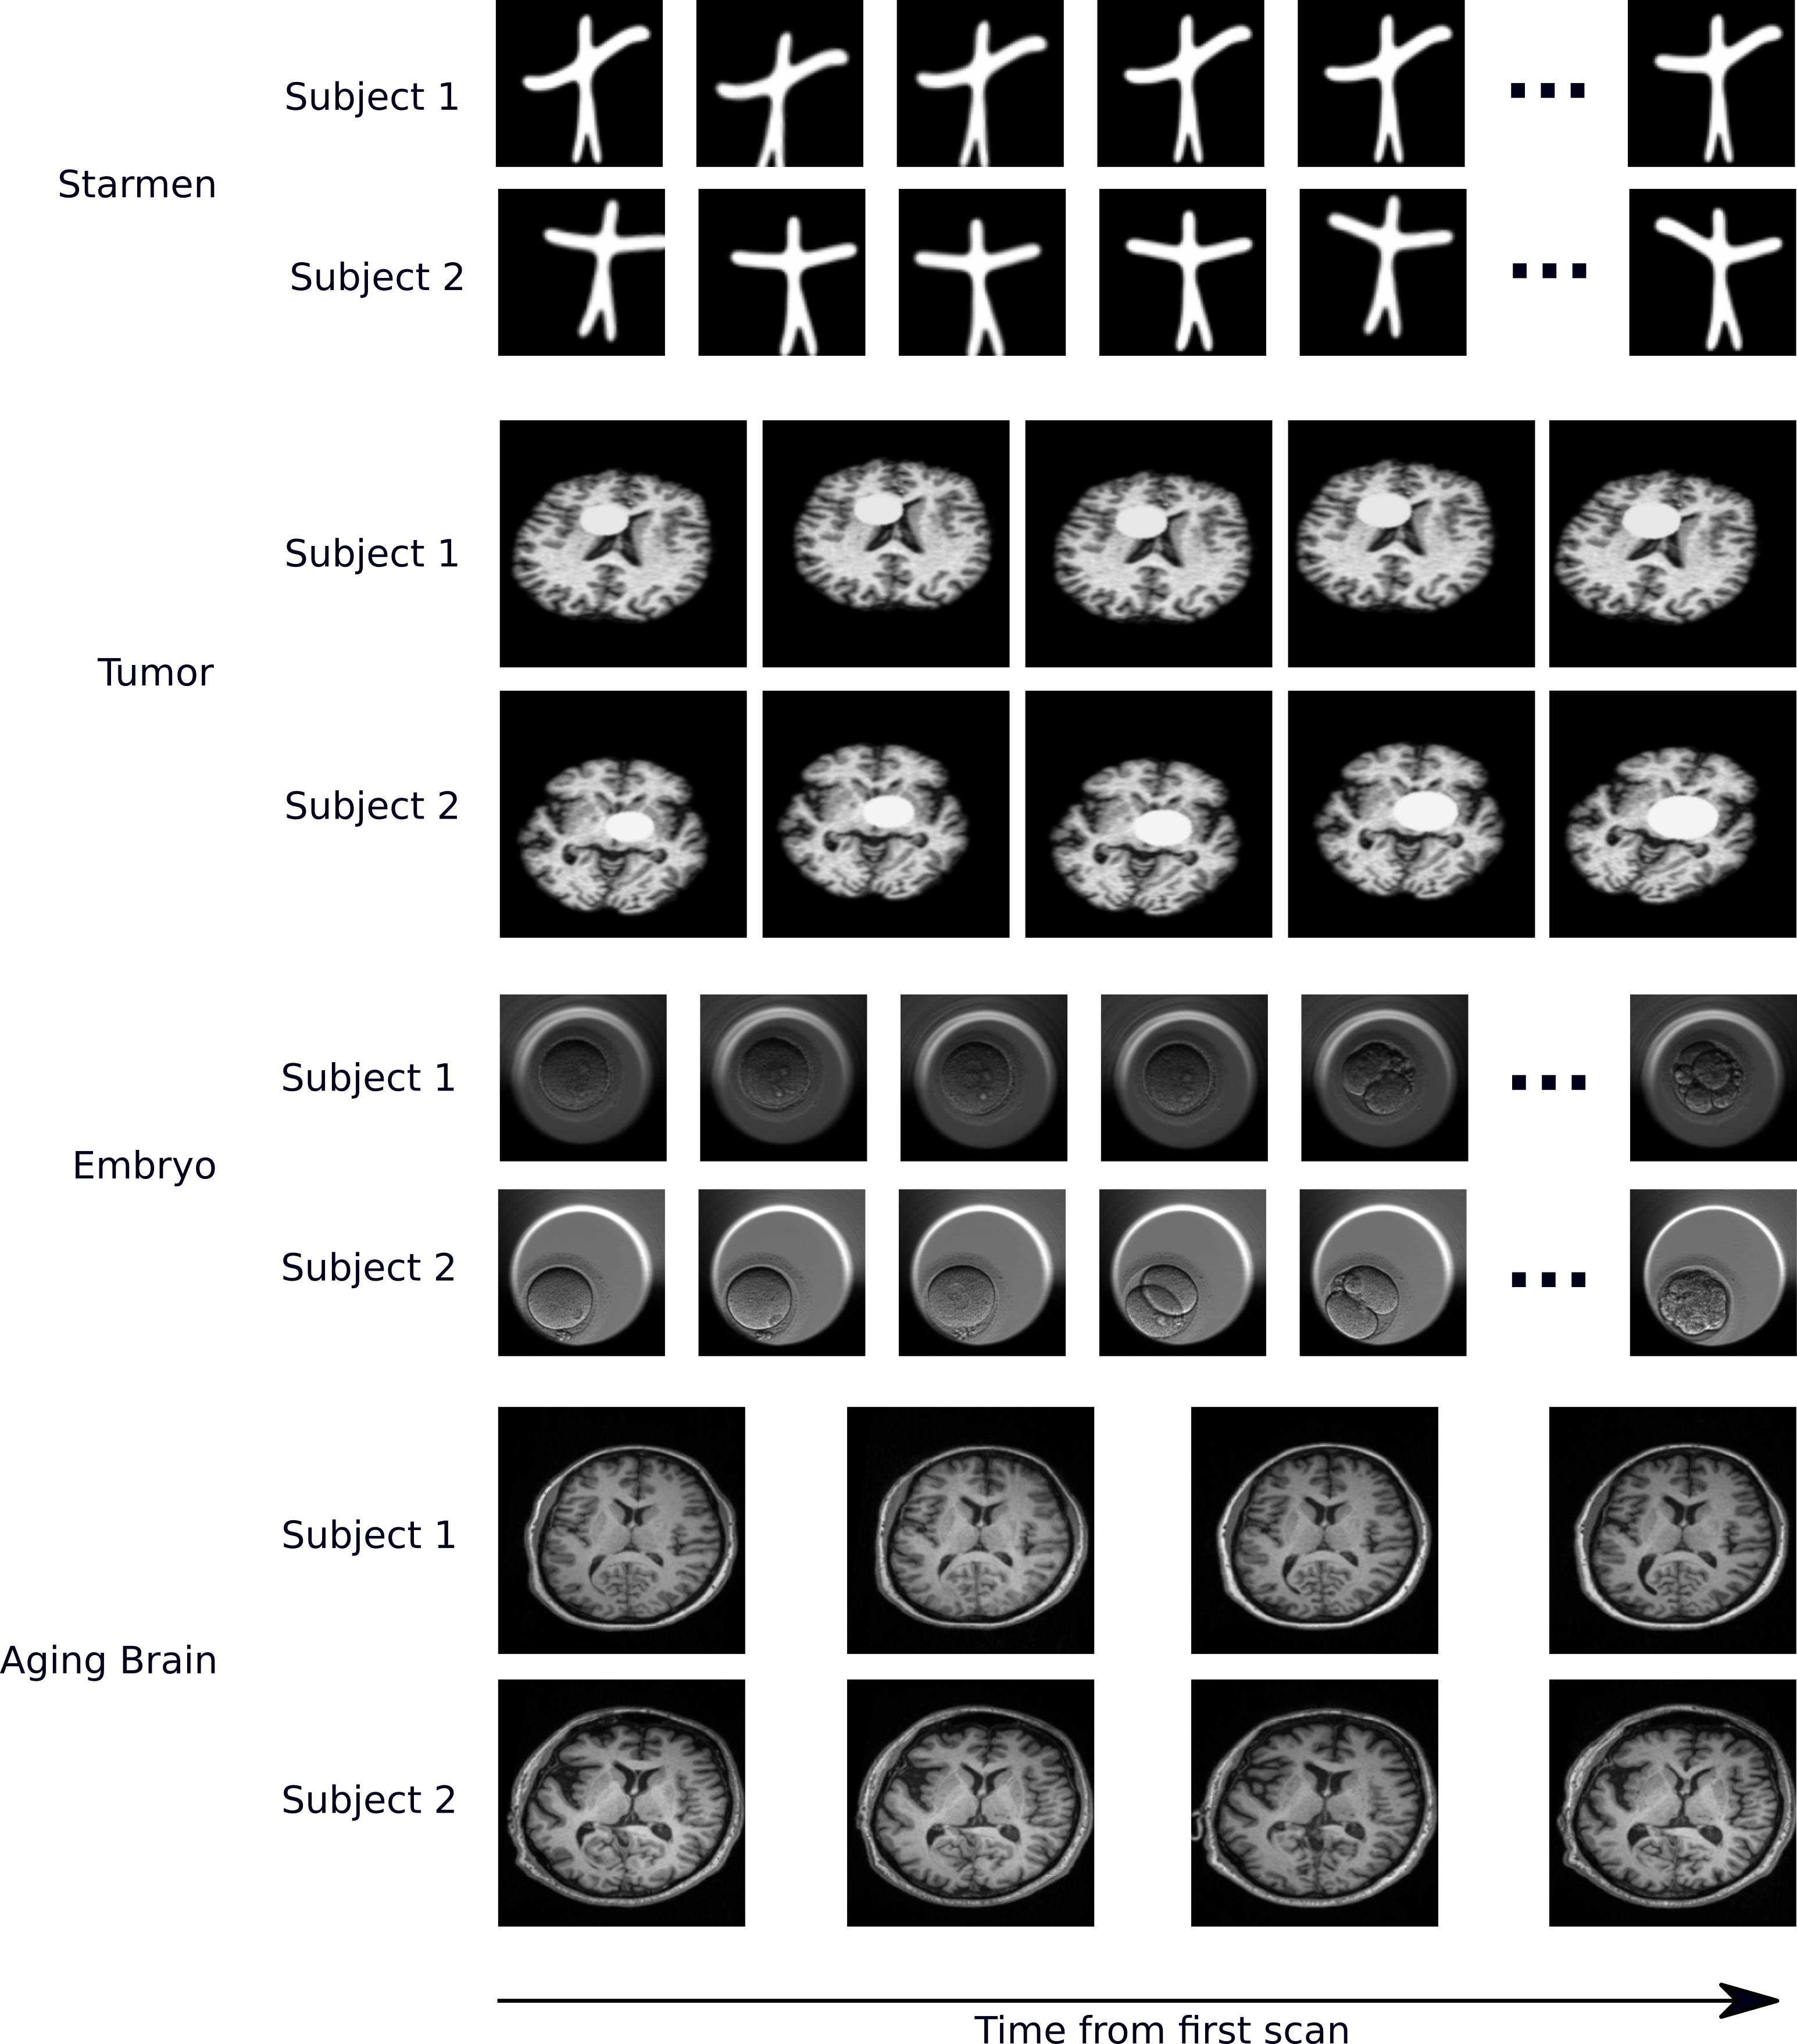

We used two synthetic datasets and two real-world datasets to explore the utility of the proposed approach. All four datasets have sets of images that temporal change is monotonic and irreversible. We used 0.6/0.2/0.2 ratio for the train/validation/test split, except for the Starmen. The split is done at the subject level. \figurereffig:data in Appx. A shows some representative examples of each dataset.

Starmen. The public synthetic Starmen dataset has been used for evaluating longitudinal frameworks [Bône et al. (2018), Couronné et al. (2021)]. Raising the left arm is the only temporal change within a subject and parameterized individually in the original dataset. The dynamics of change is characterized by an affine reparametrization of time as follows: , where and are subject-specific parameters. For additional subject variability, we randomly rotated (uniform between -10 and 10 degrees) and translated with (-6.8,6.8) pixels. Out of 1000 sets of 10 longitudinal images, 400 sets of images are used for training, 100 sets for validation, and the rest for testing. The ground-truth progression value is ranged in .

Tumor. A synthetic tumor growth dataset was created using real T1-weighted brain MRIs from 72 healthy subjects in OASIS-2 [Marcus et al. (2010)]. The images were preprocessed (brain extraction and intensity normalization) using in-house software and co-registered using [Avants et al. (2009)] to add synthetic longitudinal change and nuisance effect. Tumors were synthesized as discs, randomly placed within the brain tissue of the mid-axial slice. The tumor intensity, initial size, and speed of growth were randomly selected. We generated 3-5 time points per subject. In total, 292 synthetic images with an average tumor size of pixels were generated. All images were randomly rotated and translated with (-10, 10) degrees/pixels.

Embryo. We used the real embryo development dataset collected using time-lapse imaging incubators in an IVF study [Gomez et al. (2022)]. The images of developing embryos are fully annotated with 16 development phases. We used embryos with multiple phases and selected one image per phase. In total, 7784 images from 698 embryos were used. The embryos have on average phases.

Aging Brain. Structural MRI images from OASIS-3 [LaMontagne et al. (2019)]. In total, 754 T1-weighted images from 272 healthy subjects ranging in age from years (with a mean and std of ) at the initial scan were used. The subjects have time-points. We only use the mid-axial slice of linearly aligned images [Avants et al. (2009)].

Appendix A Dataset

fig:data shows examples of four datasets. Note the nuisance variation is different in each dataset. The position of the left arm in Starmen, the size of the tumor in Tumor, the phase of cells in Embryo and the structural change of the brain in Aging Brain are the meaningful temporal change. Other changes are the nuisance variation.